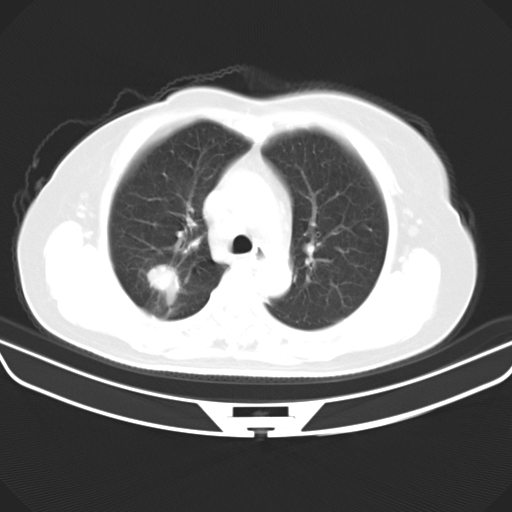

以下是引用zjzjr在2007-3-23 13:28:00的发言:[br]右肺上叶后段可见一结节状高密度影,可见毛刺征,胸膜凹陷征及血管导入征,纵隔内可见肿大淋巴结影.考虑右肺上叶周围型肺癌伴纵隔淋巴结转移.

以下是引用zjzjr在2007-3-23 13:28:00的发言:[br]右肺上叶后段可见一结节状高密度影,可见毛刺征,胸膜凹陷征及血管导入征,气管前腔静脉后可见肿大淋巴结影.考虑右肺上叶周围型肺癌伴纵隔淋巴结转移.